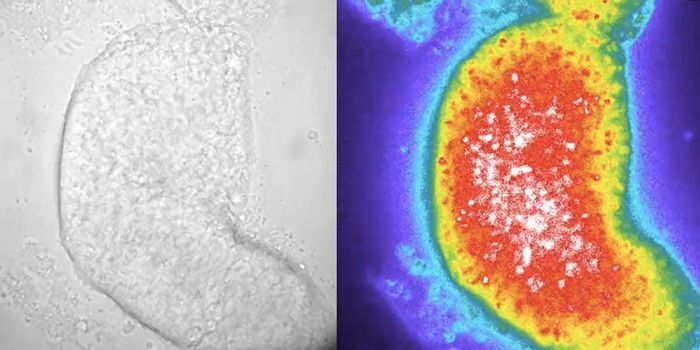

SEP 24, 2021Cell & Molecular BiologyThis photo by Sozen & Jorgensen et al., Nature Communications, shows an embryo-like structure made from human stem cells ...